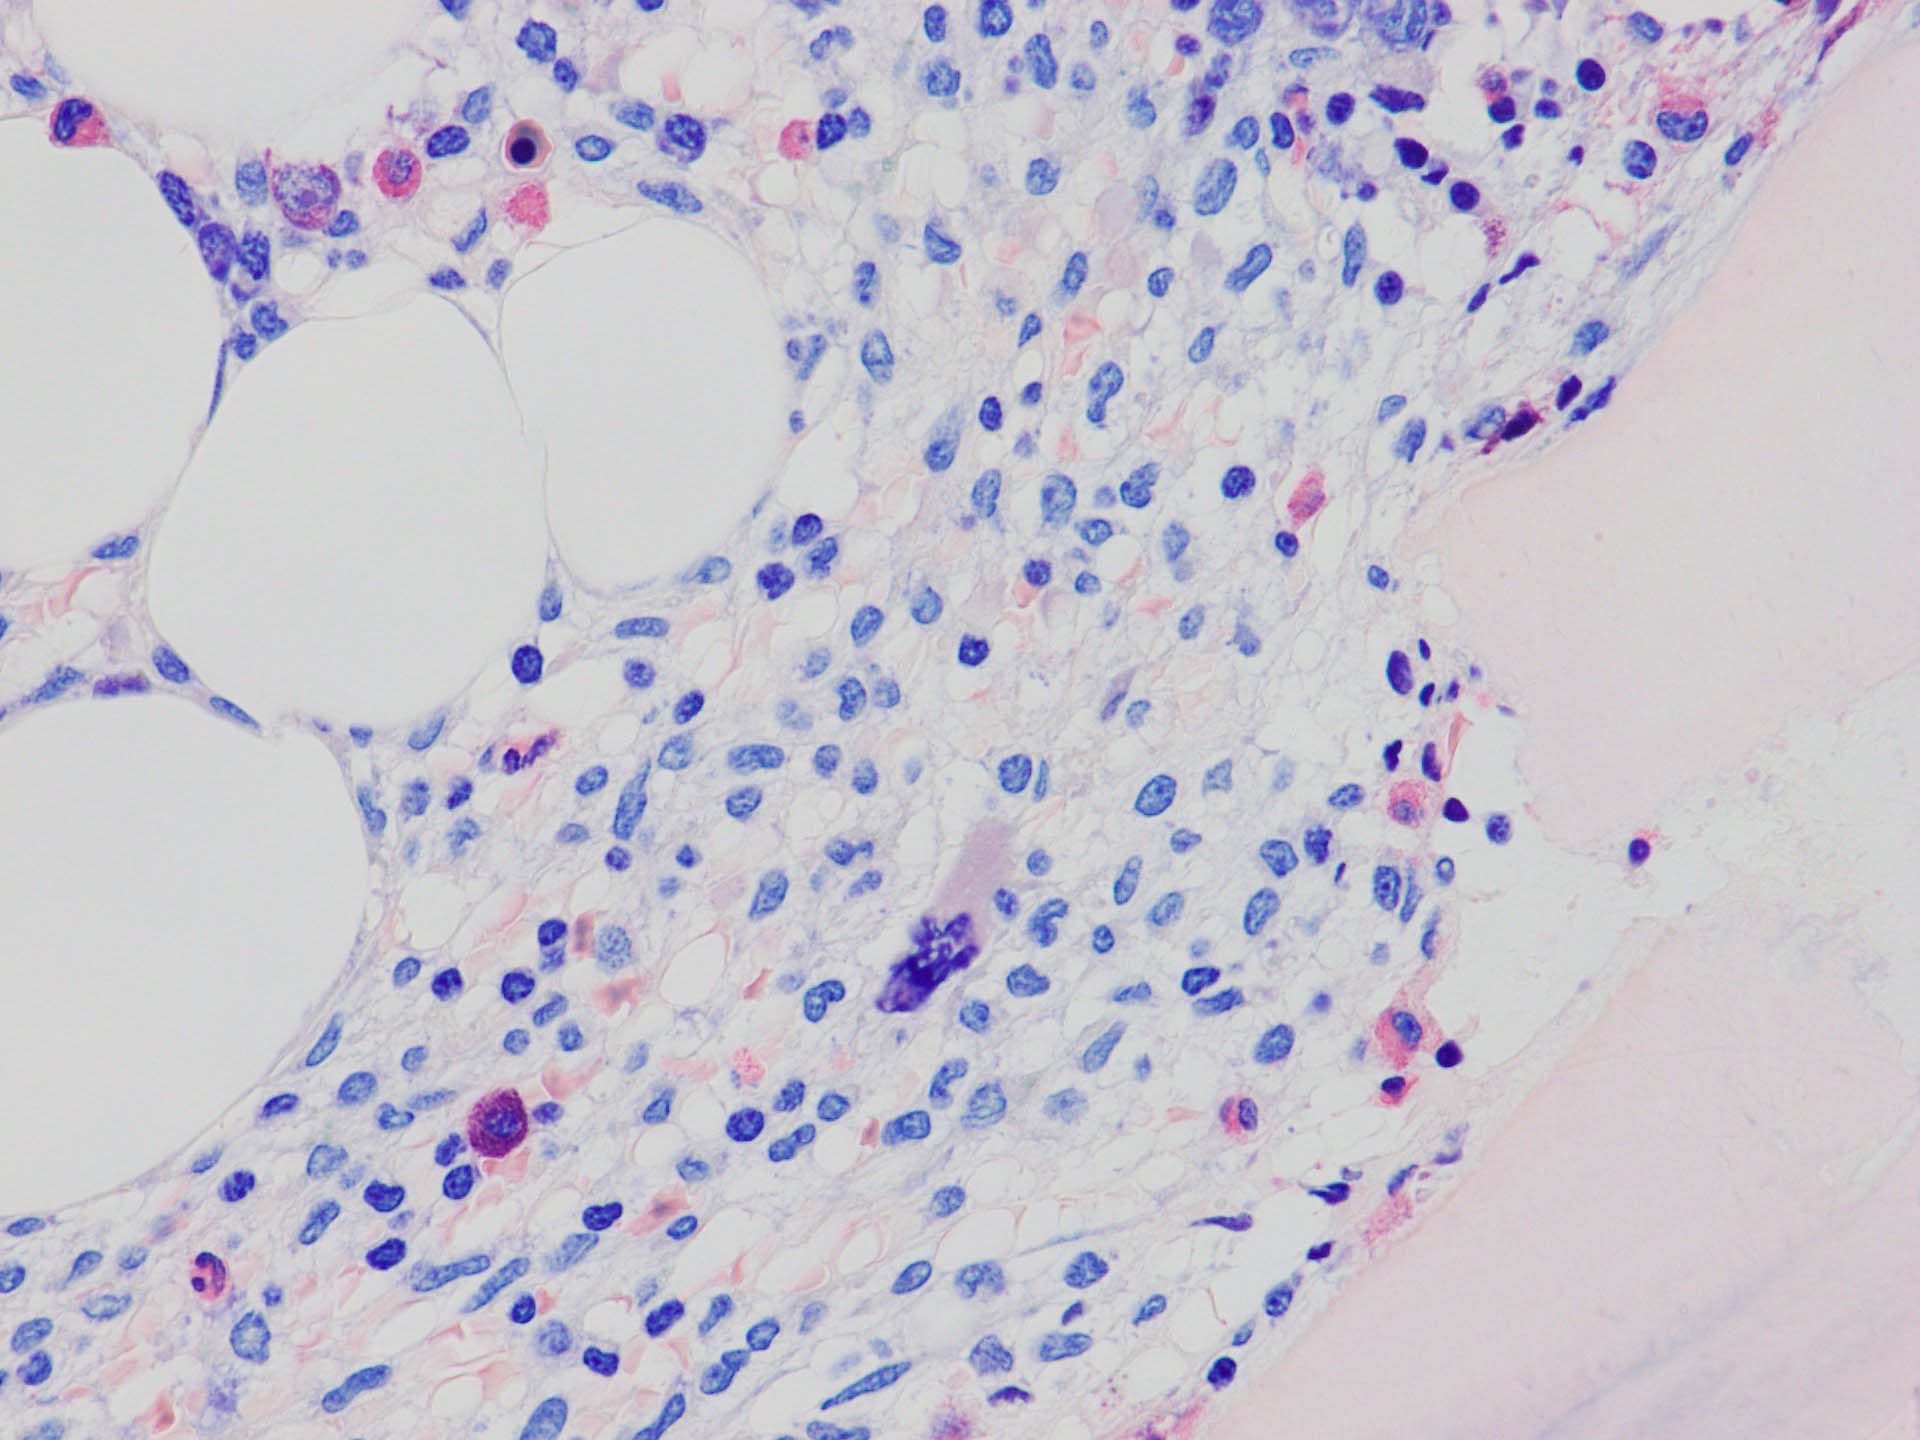

ASD-G 低倍率所見では赤芽球血島は幼若赤芽球の集簇巣が散在する, 顆粒球系細胞(ASDに赤く染色される)は減少,granulopoietic hypoplasiaを呈する.疎な集簇を示すmast cellsの増加がある.

ASD-G陰性の細胞がびまん性に増加しているように見える.

ASD-Giemsa陰性の細胞がシート状に増殖する. 核はクロマチン濃染, 核小体は不明瞭.類円形, 卵円形, くびれを持つ多稜形核, 長円形いびつで屈曲した核, など多彩. 細胞質は淡清色調, 広く淡明. 赤芽球血島は幼若赤芽球のみで形成される異形成像を示す. やや離れて成熟赤芽球が疎な集簇を示す.

Ag染色では, 疎な弾性線維が増生し,増殖細胞を小胞巣状に分画するいわゆる「lymphomatoid pattern」を呈する. 本例では, Mgkに異形成所見がある.